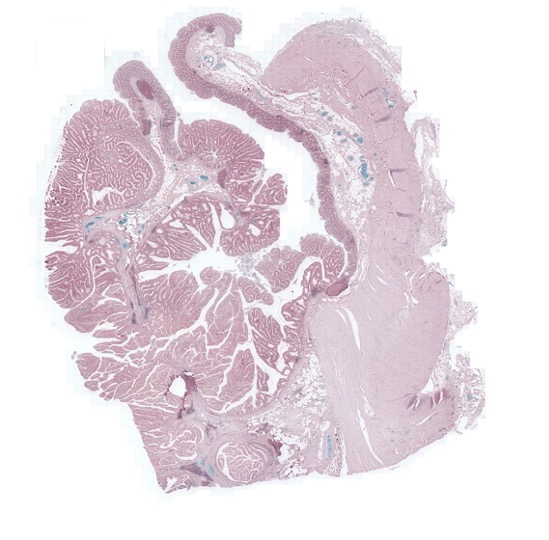

FigureΒ 2 shows the registration results for pathology images where we show the reference and floating images alongwith the misalignment images before registration and after registration using SR-Net and SR-Net. The misalignment is greatly reduced after registration using SR-Net while in the case of SR-Net there is still some resulting misalignment. This error can have significant consequences in the final diagnosis workflow. Hence the advantages of self-supervised segmentation maps are quite clear.

![]() |

| (a) | (b) | (c) | (d) | (e) |